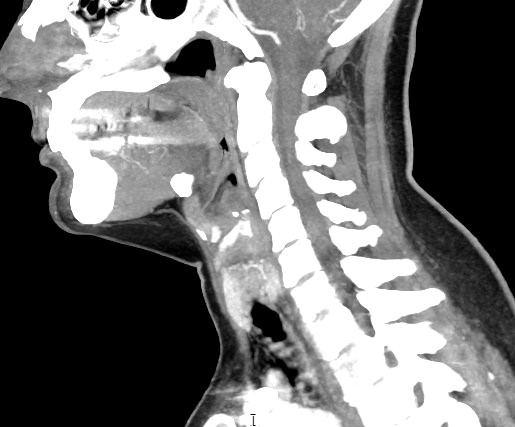

В компьютерном томографе излучатель рентгеновских лучей установлен в кольцевой части аппарата и, непрерывно вращаясь вокруг зоны исследования, производит послойное сканирование в различных плоскостях. В результате получаются снимки анатомической зоны в мельчайших подробностях, а после цифровой обработки полученных данных – точные трехмерные объемные модели исследуемой области. При этом изображения органов можно приблизить, повернуть в разные стороны, что значительно повышает точность диагностики различных заболеваний.

Для улучшения визуализации мягкотканных структур (внутренних органов, клетчаточных пространств, связок, мышц, сухожилий, кровеносных сосудов и лимфатических узлов) в ряде случаев проводится дополнительно контрастное усиление. Для этого пациенту внутривенно вводится йодсодержащий контрастный препарат, который активно поглощает рентгеновские лучи. Благодаря способности контраста накапливаться в патологических участках, они становятся хорошо видны на снимках КТ. Контрастное усиление позволяет оценить состояние сосудистой системы, выявить участки воспаления и опухолевые образования. С помощью контрастирования удается выявлять опухоли минимальных размеров, определить точные размеры и границы опухоли, степень ее воздействия на окружающие ткани.